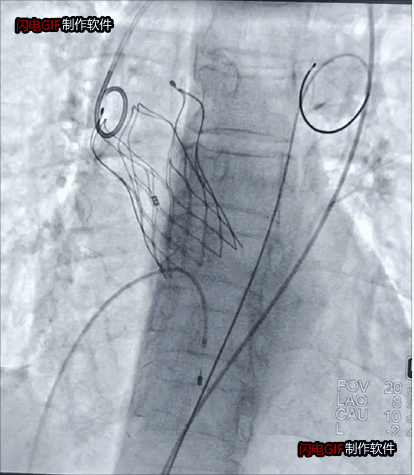

瓣狹窄患者瓣膜植入后影像

為避免激素可能對血管帶來的影響及血管入路并發(fā)癥,術(shù)前,徐州市一院心臟瓣膜病團(tuán)隊(duì)通過全面評估和檢測,為其設(shè)計(jì)了充分的應(yīng)對方案。術(shù)中,麻醉科副主任王德領(lǐng)、醫(yī)師趙盼盼克服了血壓極度波動(dòng),循環(huán)衰竭、崩潰等潛在風(fēng)險(xiǎn),為手術(shù)的順利開展鋪平道路。趙躍武在超聲科主任陳炳華、心胸外科副主任醫(yī)師嚴(yán)文俊、導(dǎo)管室護(hù)士長孫寧帶領(lǐng)的護(hù)理和技師團(tuán)隊(duì)的通力配合下,經(jīng)反復(fù)確認(rèn)入路血管彈性和脆性后,經(jīng)左側(cè)股動(dòng)脈切開,手術(shù)圓滿完成。

國家心血管病中心心臟內(nèi)科學(xué)主任吳永健為本次手術(shù)提供了遠(yuǎn)程指導(dǎo)。本次手術(shù)還邀請了徐州醫(yī)科大學(xué)附屬醫(yī)院心血管內(nèi)科主任醫(yī)師王誠和醫(yī)師程守全的合作,體現(xiàn)了徐州本地醫(yī)者的團(tuán)結(jié)協(xié)作和無私無畏。